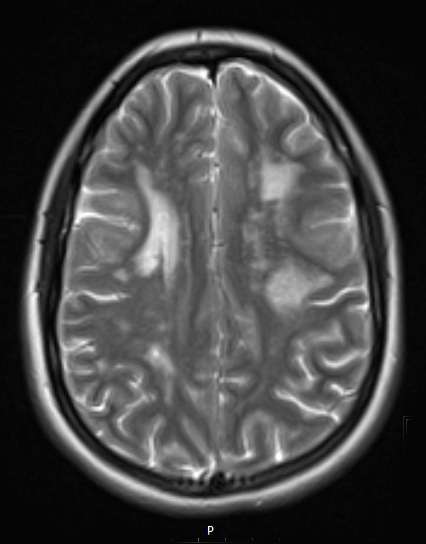

Lesions are hyperintense in this T2-weighted scan without contrast. ---- MRI Comment: Some of these MRI lesions were ovoid, well demarcated, perpendicular periventricular lesions, as well as a corpus callosum genu lesion. These lesions have an appearance which could be seen with demyelinating disease but are atypical considering the degree of diffusion restriction, T1 hypointensity without contrast enhancement; this MRI appearance was thought more typical of ischemic disease. There were older areas of encephalomalacia were likely prior subclinical ischemic events. The clinical impression was that of an inherited arteriopathy, most likely CADASIL.